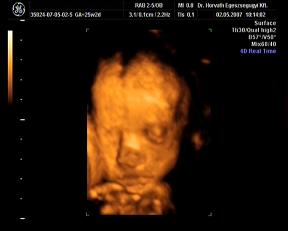

Néhány kép, nagyon kis drága volt, szépen mutatta magát:

egy 2D-s profil

És néhány 3D-s:

Kép Kép Kép Kép

Hát ilyenek vagyunk a 25. héten.:D